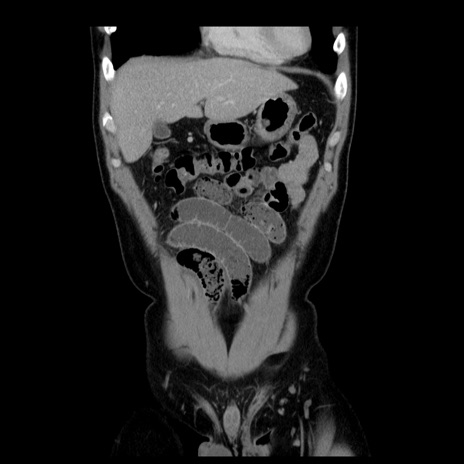

症例4(冠状断像)

【症例】30歳代男性

【主訴】腹痛、嘔吐

【現病歴】昨晩から突然の腹痛あり、その後嘔吐、軟便も出現。腹痛が改善しないため救急搬送となる。2日前にしめ鯖の食事歴あり。

【身体所見】意識清明、苦悶様、BP 135/90mmHg、BT 35.7℃、腹部:平坦、やや硬、心窩部〜臍部に自発痛、圧痛あり、筋性防御+、反跳痛-

【データ】WBC 8100、CRP 0.57